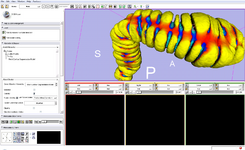

Image:PETCTFusion.png| [[Modules:PETCTFusion-Documentation-3.6 |PETCTFusion]] (Wendy Plesniak) | Image:PETCTFusion.png| [[Modules:PETCTFusion-Documentation-3.6 |PETCTFusion]] (Wendy Plesniak) | ||

PETCTFusion (Wendy Plesniak)